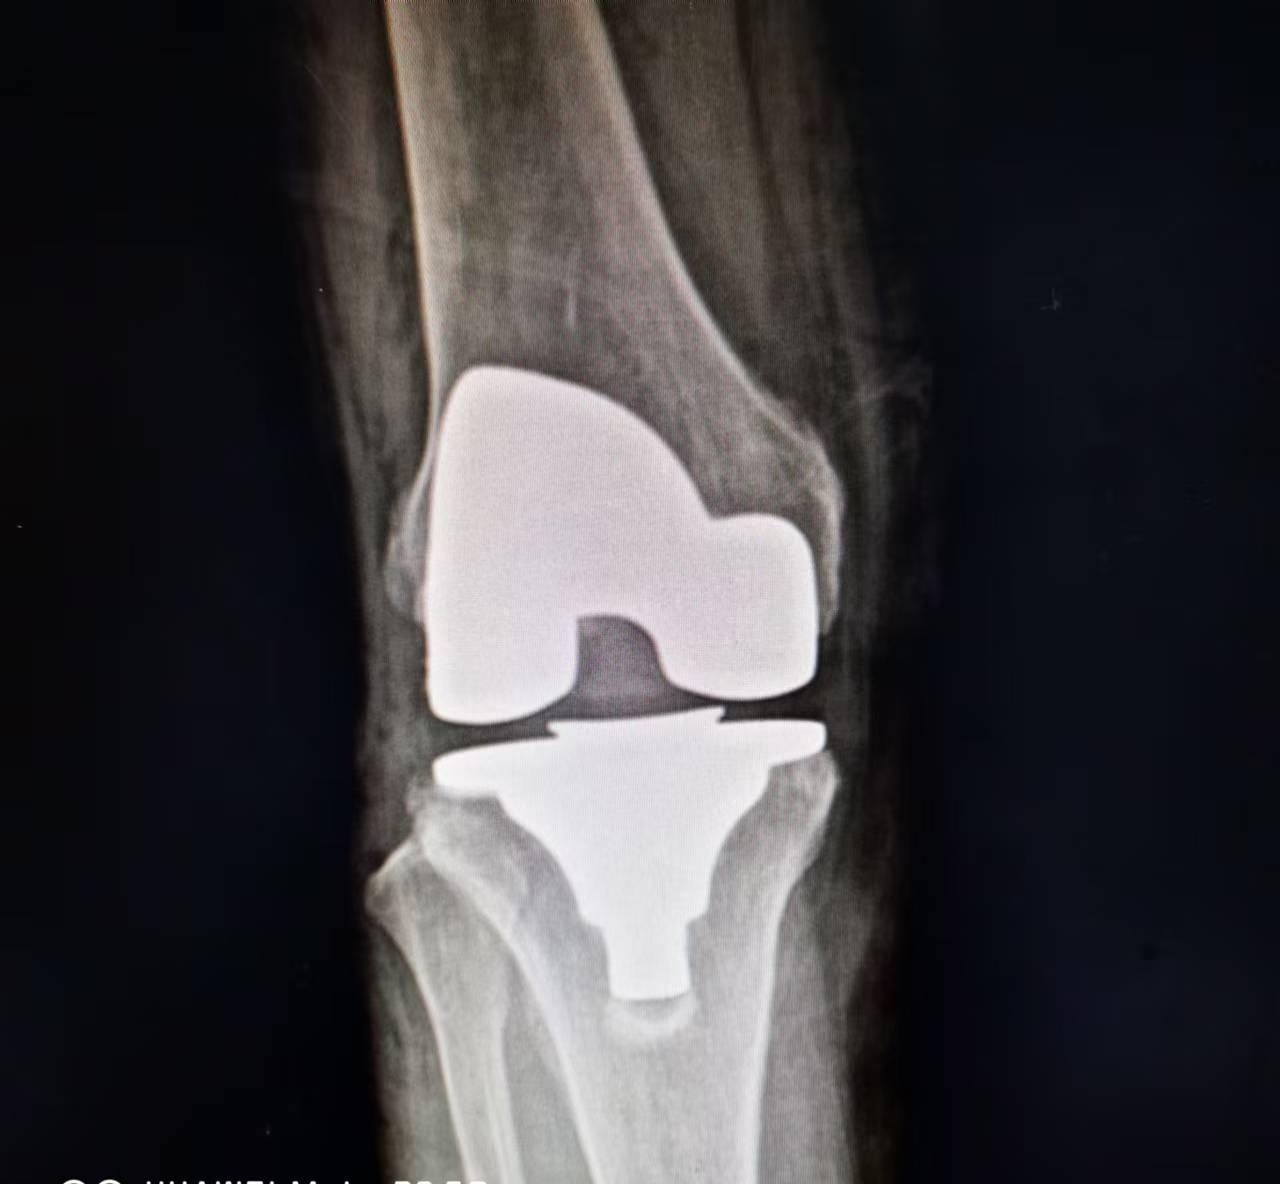

刚刚,我院骨科团队又成功完成了一台膝关节置换手术。老年女性患者,右膝退行性骨关节病多年,膝关节肿胀疼痛明显,在我院行右膝人工关节表面假体置换术。

术 后